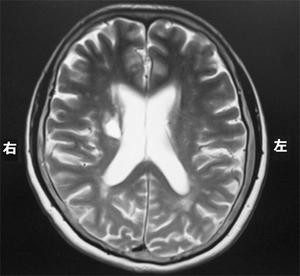

脳梗塞の発生部位によって出現する症状は異なります。この問題では、それぞれの部位における症状を正確に理解することが求められています。

右内包後脚では、左上下肢の運動麻痺が見られるため、この選択肢は正しいです。